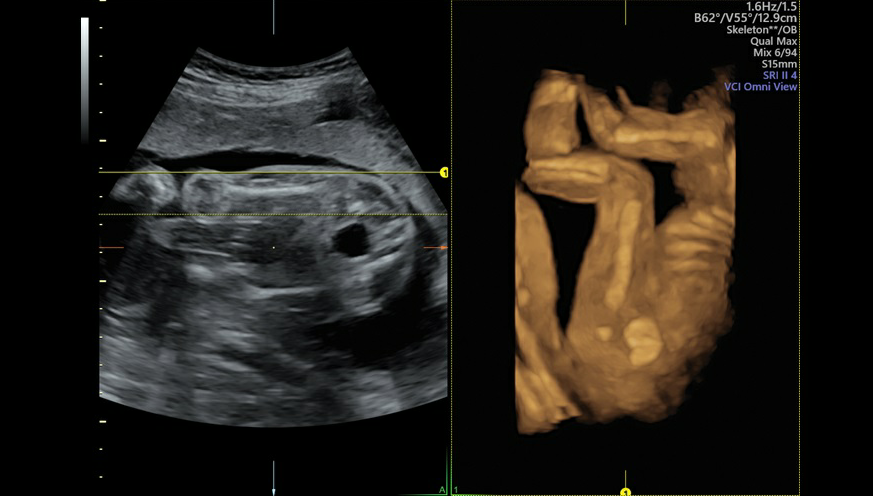

GE VOLUSON E8高端专用四维彩超

GE VOLUSON E8是目前世界上先进的彩色超声设备,被誉为“神奇彩超”,是筛查胎儿畸形的尖端设备。它提供了包括腹部、血管、小器官、产科、妇科、泌尿科、新生儿和儿科等多领域的多方面的应用。能够显示未出生的宝宝的实时动态活动图像,或者其它人体内脏器官的实时活动图像。通过四维彩超,孕妈妈躺在床上,就可以通过对面的显示屏直接和宝宝见面,还可以看到宫内胎儿,如打哈欠、伸懒腰、吮手指等等奇妙的动作。

Voluson E8的3D/4D容积超声技术已经得到了世界范围的广泛认可,Voluson E8除了保持Voluson产品在3D/4D的成像技术优势以外,在2D图像质量,彩色灵敏度方面有很大提高外,在核心技术如探头、波束形成器、成像模式、人机工程方面,均有了革命性的提高。该系统满足了临床超声医学专家在图像质量、人机工程、工作流程、腔内探头等几个方面提出的期待和希望。